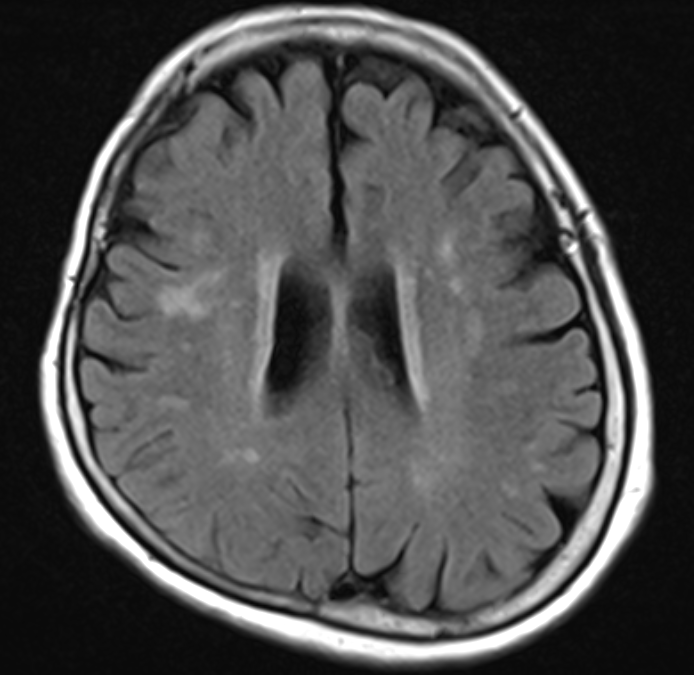

그중 대표적인 경우가 뇌 MRI 검사에서 흰 점이 발견되는 경우이다.(그림 1 참조) 초기 뇌졸중이나 미니 뇌졸중이라고 불리기도 하며, 정체를 알 수 없는 이 흰 점은 과연 무엇일까요?

우리는 정체를 알 수 없는 외계 비행물체를 UFO(Unidentified Flying Object)라고 부르는데, 마찬가지로 뇌에 존재하는 정체를 알 수 없는 흰 점을 UBO(Unidentified Bright Object)라고 부릅니다. 즉, 흰 점인데 정체를 알 수 없다는 뜻이죠. MRI상에서 정확히 결론을 내릴 수 없고 일단 사진 상에서 보이므로 UBO라고 표시하게 됩니다.